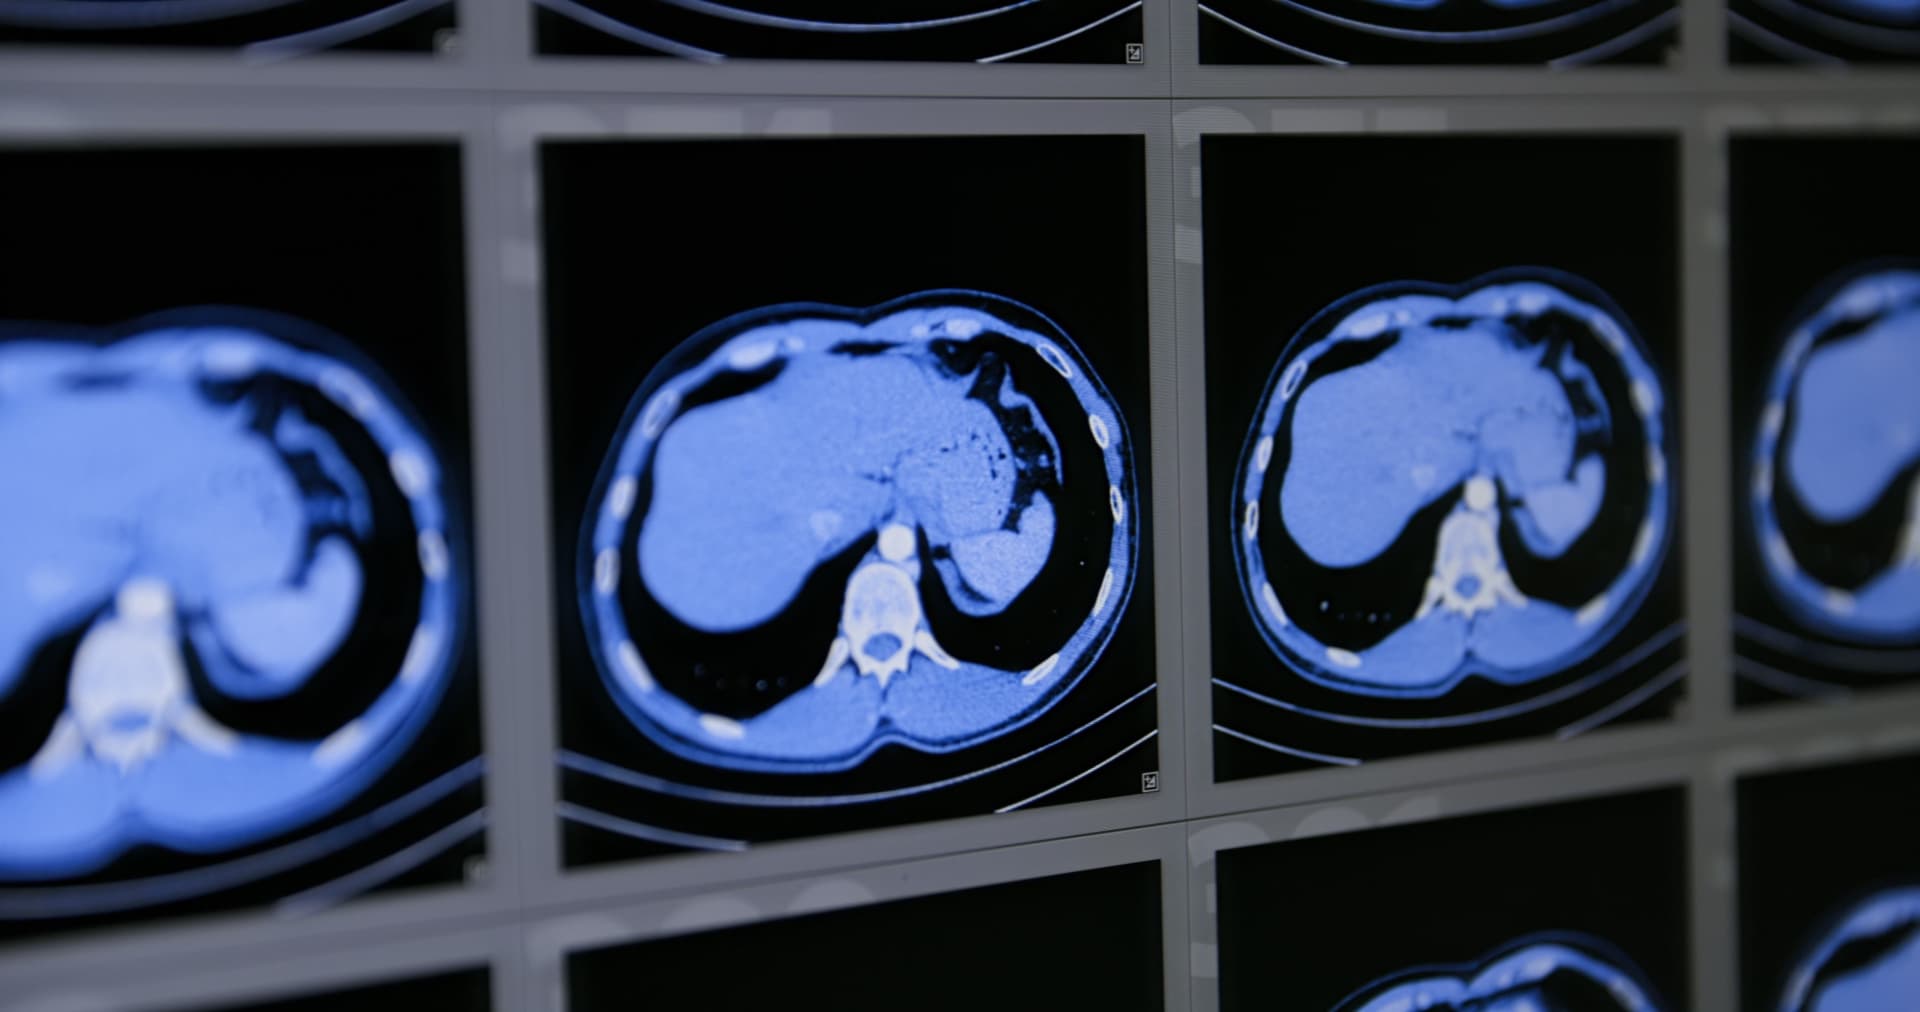

CT or MRI Scan

Detailed imaging to evaluate the liver, pancreas, and biliary system when ultrasound findings are inconclusive.